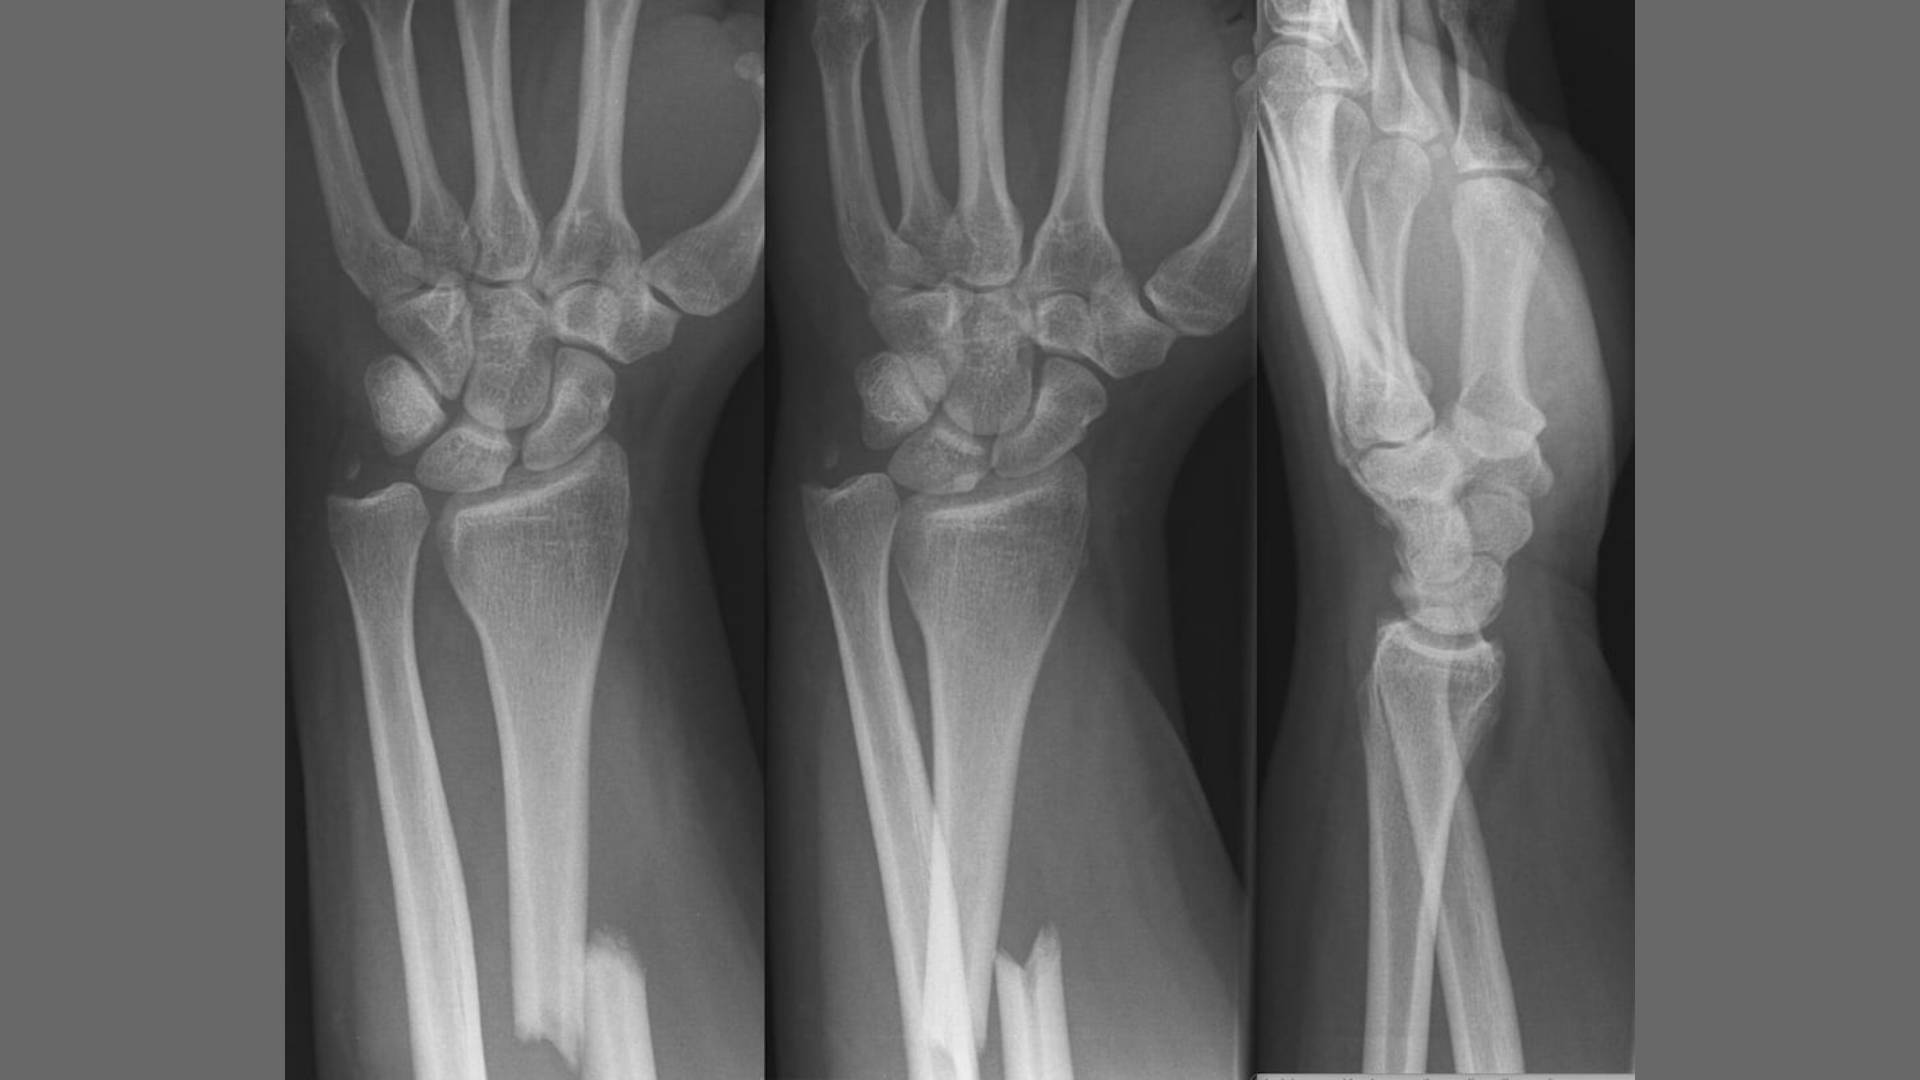

Chụp X-quang

X-quang là phương tiện hình ảnh cơ bản và bắt buộc trong chẩn đoán gãy Galeazzi. Cần chụp cả hai tư thế thẳng và nghiêng của toàn bộ cẳng tay, bao gồm cả khớp cổ tay và khớp khuỷu tay, để không bỏ sót các tổn thương liên quan. Hình ảnh thường cho thấy gãy xương quay ở đoạn một phần ba dưới, với hoặc không có di lệch. Đặc biệt, cần quan sát kỹ mối liên hệ giữa đầu dưới xương trụ và xương quay để đánh giá tình trạng khớp quay - trụ dưới. Các dấu hiệu gợi ý trật khớp bao gồm khoảng cách bất thường giữa hai xương, lệch trục hoặc mất liên tục cung khớp cổ tay.

Trong trường hợp hình ảnh trật khớp quay - trụ dưới không rõ ràng trên phim X-quang, có thể chụp cổ tay đối bên để so sánh. Điều này đặc biệt hữu ích ở những bệnh nhân có cấu trúc giải phẫu không điển hình hoặc nghi ngờ tổn thương nhẹ nhưng vẫn có triệu chứng lâm sàng gợi ý.